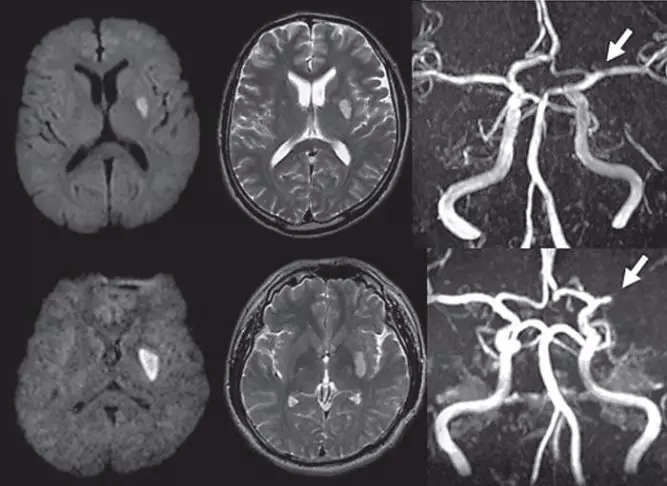

先看图 。 图2上层与下层所示 , 均为左侧基底节区梗死 , 前者最大梗死直径12.7mm , 后者最大梗死直径23.4mm[2](图1) 。 如果仅仅依据病灶大小 , 则前者可能被认定是腔梗 。 实际上 , 两者均为左侧大脑中动脉病变 , 前者狭窄后者闭塞 。

按照既往的概念 , 腔隙性梗死是颅内大动脉的深穿支动脉闭塞引起 , 病变部位常位于基底节或脑干白质内 , 病灶大小通常小于15~20 mm 。

这里涉及两个问题:其一 , 腔梗 , 最主要的诊断标准是依据病灶大小 , 也就是病灶直径 , 属于组织学或结构学诊断;其二:颅内外大动脉型病变和心源性栓塞 , 均可能导致腔梗 , 腔梗的病因很难准确界定 , 属于排除性诊断 。

因此 , 不管是尸检还是影像学检查 , 诊断腔梗都是依据梗死病灶大小和部位 。 如果病灶超过15~20mm范围 ,一般便不会诊断为腔梗 , 但是 , 其责任血管依然是可能是深穿支动脉 。 因此 , 依靠病灶直径判定腔梗 , 是时代局限性不得已而为之 , 是有争议的 , 业已受到挑战 。

韩国Kim团队早在2007年就发表文章 , 对以15mm大小作为腔隙性脑梗死诊断提出疑问[2] 。 图1所示脑梗死正是文中配图 , 直观显示病灶大小不能确定梗死类型 。